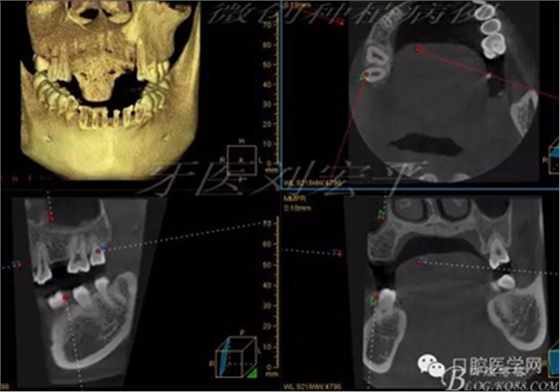

術(shù)后CT截圖